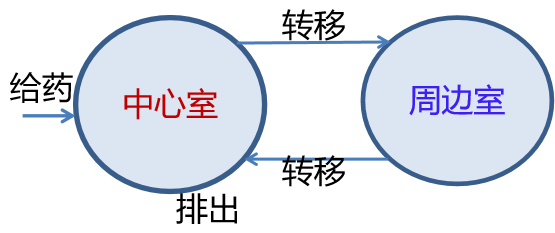

房室模型(Compartment Model)是将机体分为血液较为丰富的中心室(心、肝、肺、肾等)和血液较为贫乏的周边室(四肢、肌肉组织等),药物的动态过程在每个房室内是一致的,转移只是在两个房室及某个房室与体外之间进行。

下面只考虑房室之间、房室与体外转移速率为常数的二房室模型(乳突状模型),如图13所示。

图13 二房室模型